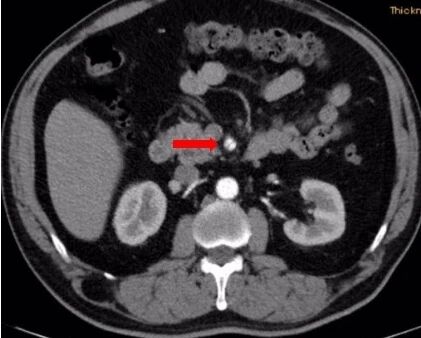

术前查腹腔动脉CTA示:肠系膜上动脉夹层伴动脉瘤。

患者肠系膜上动脉夹层动脉瘤,真腔明显缩小,假腔增大,有胃肠道缺血表现,有手术指征,未见手术禁忌。

术前造影图像